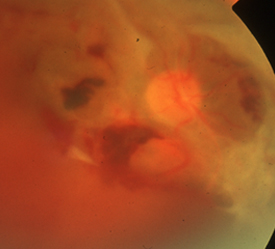

虚血部分に酸素や栄養を送り込もうと、新生血管が網膜の表面や硝子体に伸びてきます。薄い膜状の増殖膜が形成されたり、新生血管が破れることで硝子体出血、増殖膜が網膜を牽引することで網膜剥離が生じます。

増殖網膜症で硝子体出血を除去したり、網膜剥離を元に戻したりする手術です。

糖尿病黄斑症の治療のために行うこともあります。